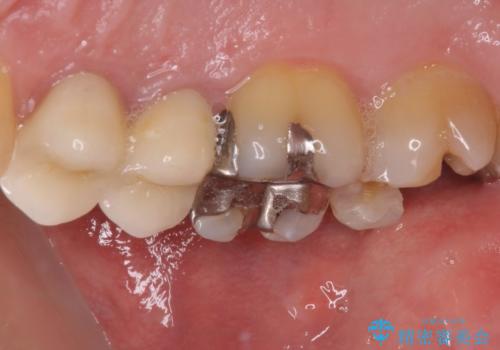

- 上の奥歯に装着されていた銀歯が外れてしまったとのことで来院された患者様です。

強い咬合力により銀歯と歯の間に隙間ができ、その隙間から虫歯となって外れてしまったと想像されました。

銀歯では歯と充填物の固さに違いがあり、再度外れてしまうリスクが高いため、固さが歯と近いゴールドインレー(PGAインレー)にて修復することとしました。